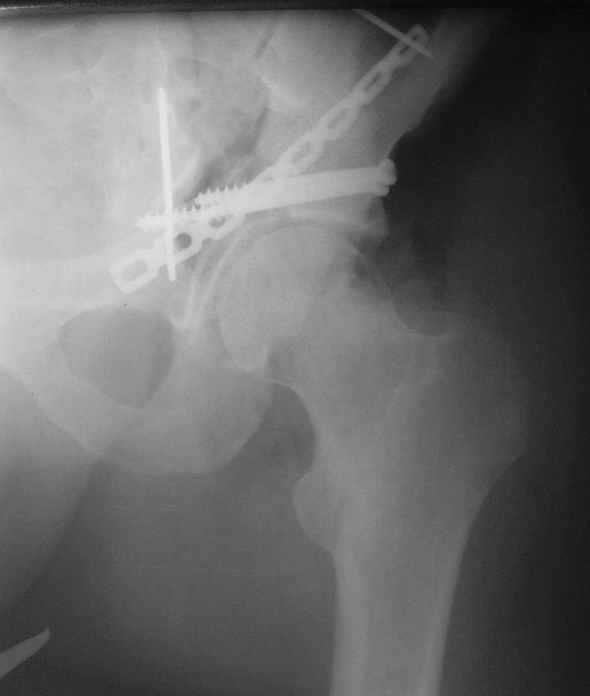

Высылаю пример еще одного случая, остеосинтез пластиной из подвздошного доступа.

Анатолий, во второй презентации, какой Ваш диагноз, не поперечный ли перелом ацетабулум? Вы написали, Ваш доступ был подвздошный, по моему мнению, ваш доступ лимитировал Вас к anterior column и постоянно надо было держать в контроле за натяжением femoral artery and vein, иначе грозит закупоркой артерии или вены, (были и такие experience), при сгибании в тазобедренном суставе, которое ухудшает и так ухудшенный доступ. По-моему, если доступ расширить, т.е. formal Ilioinguinal approach то применить пластину подлиннее 12-14 дырок на pelvic brim, через первое окно Ilioinguinal approach, т.е. Symphisis side, после рассечения места прекрепления muscle rectus abdominus, где достаточно места для 4 шурупов, тогда таким образом фиксированный перелом держится более стабильно и 4.5 мм шурупы для колонн можно было бы пропустить через пластину кзади впадины.